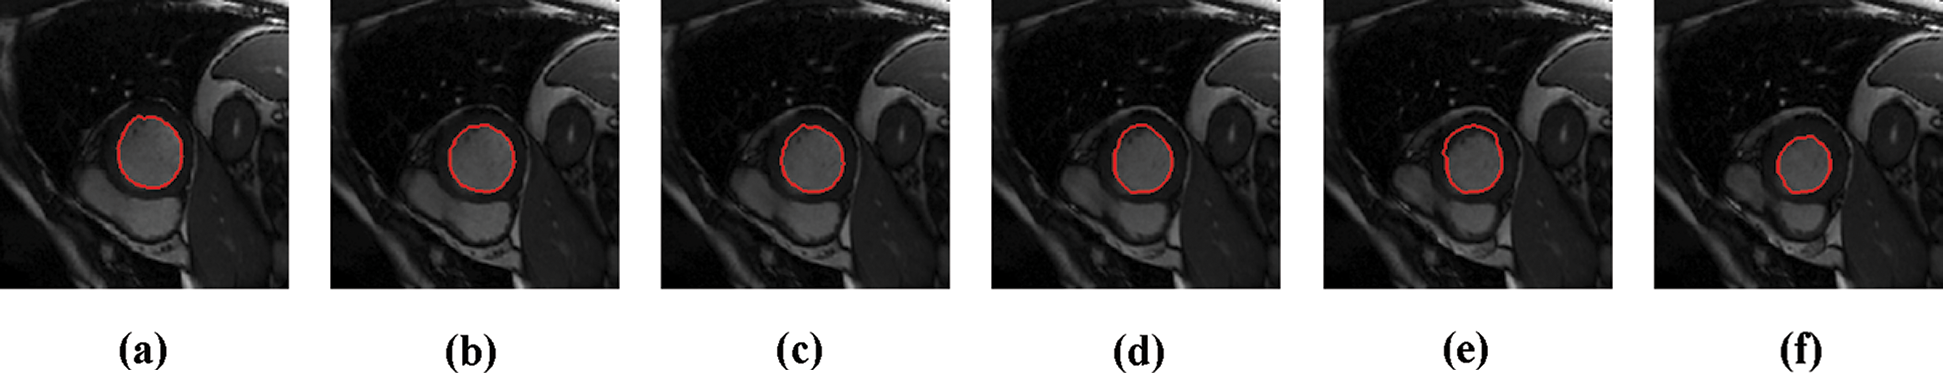

The experimental results are categorized into two distinct sections to underline both the segmentation and psoriasis lesion localization results. The presented results of this paper were obtained through using different 6 techniques to 300 sets of CVD. In this paper, multi-axis CMR database was used in three axes for 6 case studies to provide the results of various segmentation schemes. In this section, the employed techniques for studying and segmenting medical images are executed using MATLAB. Figs. 1a–1f present the Caselles segmentation technique results. These results indicate that this technique gives better results when the initialization step is suitable and the image has a high intensity gradient at the edge between the cavity and the myocardium of LV. It is also clear from the results that the blood pool segmentation depends on the boundary features. Both of Li and Bernard segmentation techniques show a wide band segmented results that are not reasonable to the blood pool segmentation as shown in Figs. 2 and 3. This is apparently visible in the Bernard segmentation technique where the segmentation partitions of each slice to bright regions and dark regions cannot separate the LV cavity from other parts of the image. The relationship between each pixel and its adjacent neighbors is considered. As it could be seen from Figs. 4a–4f, the blood pool of LV is purely delineated. That is the resulted segmented image of the Chan-Vese technique appears well-defined. Based on the obtained results, one can say Chan-Vese technique works well with homogenous regions such as cardiac images. In addition, the resulted segmented slices appear of high smoothing degree as well. The segmented images from the blood pool of LV obtained using the Lankton-Yezzi segmentation is presented in Figs. 5a–5f. As it could be seen from these figures, the quality of the segmentation process using the Lankton-Yezzi technique depends on the initialization. As it could be seen from Figs. 6a–6f, the two cycles of Shi-Karl segmentation technique produce good quality segmentation to the LV blood pool.

Figure 6: Sample results of Shi-Karl technique